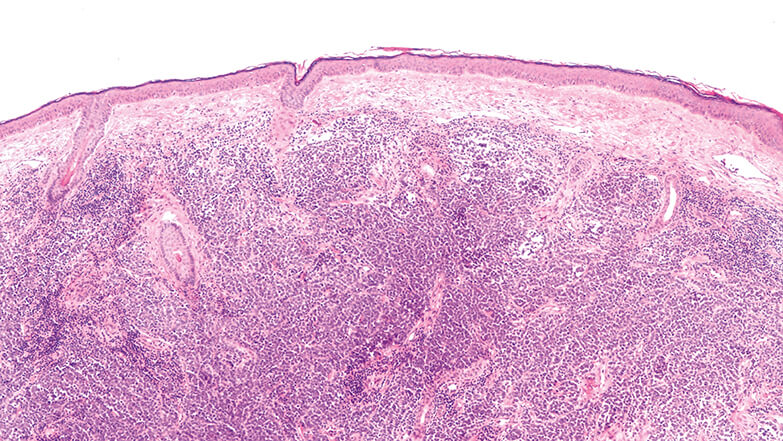

Neues zum malignen Melanom

Malignes Melanom: Sentinel-Tumorlast unabhängiger prognostischer Faktor

Update Merkelzellkarzinom